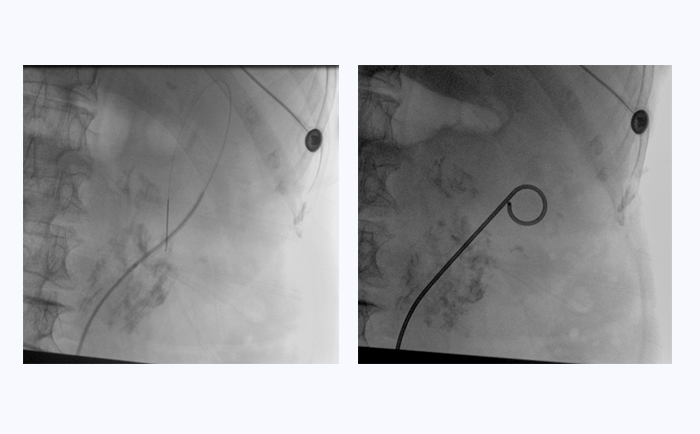

患者采用结石位进行该手术。全麻后,操作输尿管镜从尿道进入膀胱,通过镜下观察,找到输尿管开口。此时,在普爱医疗大平板一体式C形臂透视引导下,穿入导丝,到达肾盂并确认位置,同时配合输尿管镜,找到狭窄部位。接下来,同样在透视引导下,沿导丝插入双J管支架,当支架两端到达相应位置后,抽出导丝和输尿管镜,完成手术。

普爱医疗大平板一体式C形臂临床图像